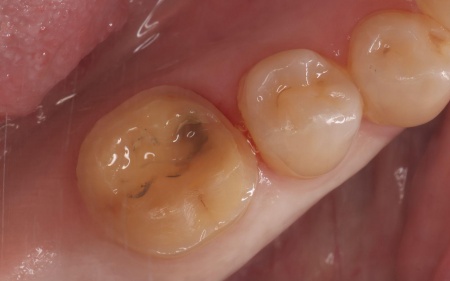

オンレーは、歯全体を覆う被せ物と比べると歯を削る量を抑えられるため、健康な歯をできるだけ残しながら、歯の強度を高めることが可能です。ただし、歯の状態によっては適応できない場合もあります。 まず、すでに装着されていた金属の詰め物を除去し、歯の状態を慎重に確認します。 次に、採取した歯型をもとにオンレーを作製します。 最後に、完成したオンレーを専用の接着剤で装着し、見た目や噛み合わせに問題がないことを確認して、治療を終了しました。 患者様の上の歯の治療についてはこちら:https://dr-kaiya.com/blog/20260312-1/ |

治療中